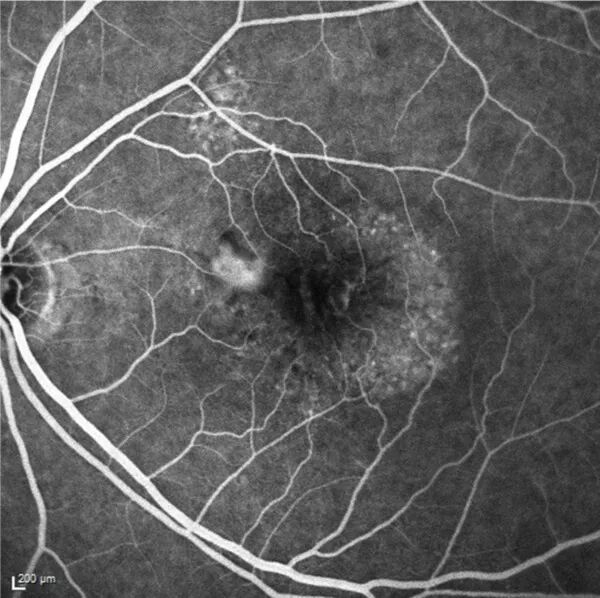

Angiography is a retinal imaging examination that allows the study of blood vessels not visible on standard fundus photographs. Its purpose is to detect vascular disorders and assess the quality of retinal vessels. It remains the gold standard for diagnosing most retinal and macular pathologies.

There are two types of angiography: fluorescein angiography and indocyanine green (ICG) angiography, which use different dyes and provide different views of the retina and choroid.